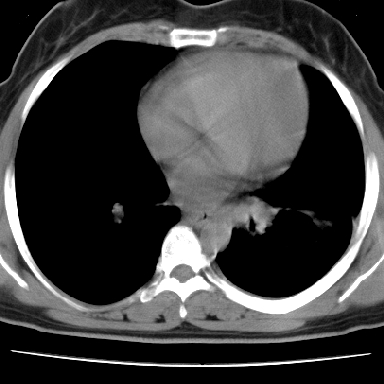

f 37 咳嗽1周,咯血1次,无浓痰,无明显发热

左下肺肿块影,内可以见小泡征,并见厚壁空洞形成,洞内缘凹凸不平,可见壁结节。靠近胸膜侧可见胸膜凹陷征。左侧胸腔内可见少量低密度积液影。右肺可见两处高致密的小结节影。

考虑:左下肺周围型肺癌伴右肺转移

左下肺肿块影,内可以见小泡征,并见厚壁空洞形成,洞内缘凹凸不平,可见壁结节。靠近胸膜侧可见胸膜凹陷征。左侧胸腔内可见少量低密度积液影。双肺可见多发性小结节影。

考虑:左下肺癌性空洞伴两肺转移